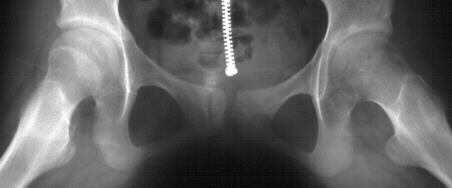

This is a 12 year old Asian female with insidious onset of left hip pain 4 months in duration. She was afebrile on presentation. Physical examination demonstrated the Left hip with 15 degrees abduction, 10 degrees adduction, 10 degrees external rotation and 0 degrees internal rotation. There was pain in left hip on range of motion and the left lower extremity was 1.5 cm longer than the right. She had an antalgic gait. The bone scan showed increased uptake at the left hip on both sides of joint. Joint space narrowing of left hip to 2 mm was noted.